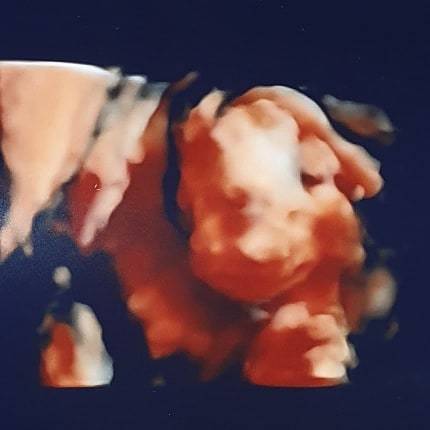

Hi all. I had a private scan today (im lucky as my family member owns a private scanning studio) They done some 2D and 3D photos for us, they also found out the sex (but we didnt) and they’ve given us a confetti cannon to pop on Christmas day which will have the colour pink or blue. Heres the photos. I also have my NHS gender scan with the hospital tomorrow for full checks. We’ll be asking them to keep the potty shot hidden for us. Baby was kicking and wriggling away on the screen today, wouldnt keep still. Yet i couldnt feel a thing, still! (He/she is camera shy and hiding their face with their hand😂) x

U@sao81 I got told the same thing today at my private scan! She said it's slightly low but could move. Feeling a little anxious, has anyone heard of this before? Here's a little image of our baby boy. I am so in love and feel so connected to him already ❤️

Due May 2020 (Thread 4)

@november90 she said to me its low and at the front but I have a really long cervix so couldn't see if it was covering. She explained that as your bump grows the placenta usually moves up, so to mention it to hospital at my next scan as they may book me in at 32 weeks for a scan to check position. Do you feel better after your scan today? The pic is fab!

I love the photo! Yours is beautiful too ❤️